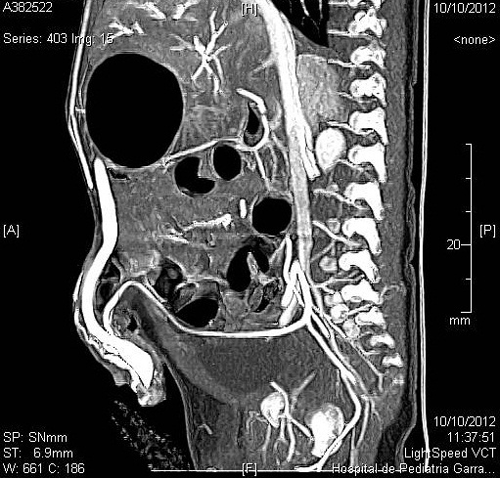

Figure 4: Umbilical AVM with inflow from the umbilical arteries and outflow via the umbilical vein.  |

A 20-day-old male neonate with an umbilical hernia was referred to our hospital because of persistent wet umbilicus. Umbilical examination showed a 2 cm diameter umbilical hernia and a long epithelialized pulsatile cord with granulomatous tissue at its end (Fig. 1). Palpable thrill was note at the midportion of the umbilical cord. Doppler ultrasonography revealed a mass at the end of the umbilical cord harboring dilated blood vessels with turbulent blood flow (Fig. 2). This vascular mass continued to the umbilical vein, which was dilated and flowed into the liver. Abdominal contrast-enhanced computed tomography revealed umbilical AVM; the umbilical arteries were patent from both internal iliac arteries, flowed into the mass directly at the end of the umbilical cord, and the dilated umbilical vein flowed out from the mass, continuing from the umbilicus to the umbilical part of the portal vein in the liver (Fig. 3, 4).